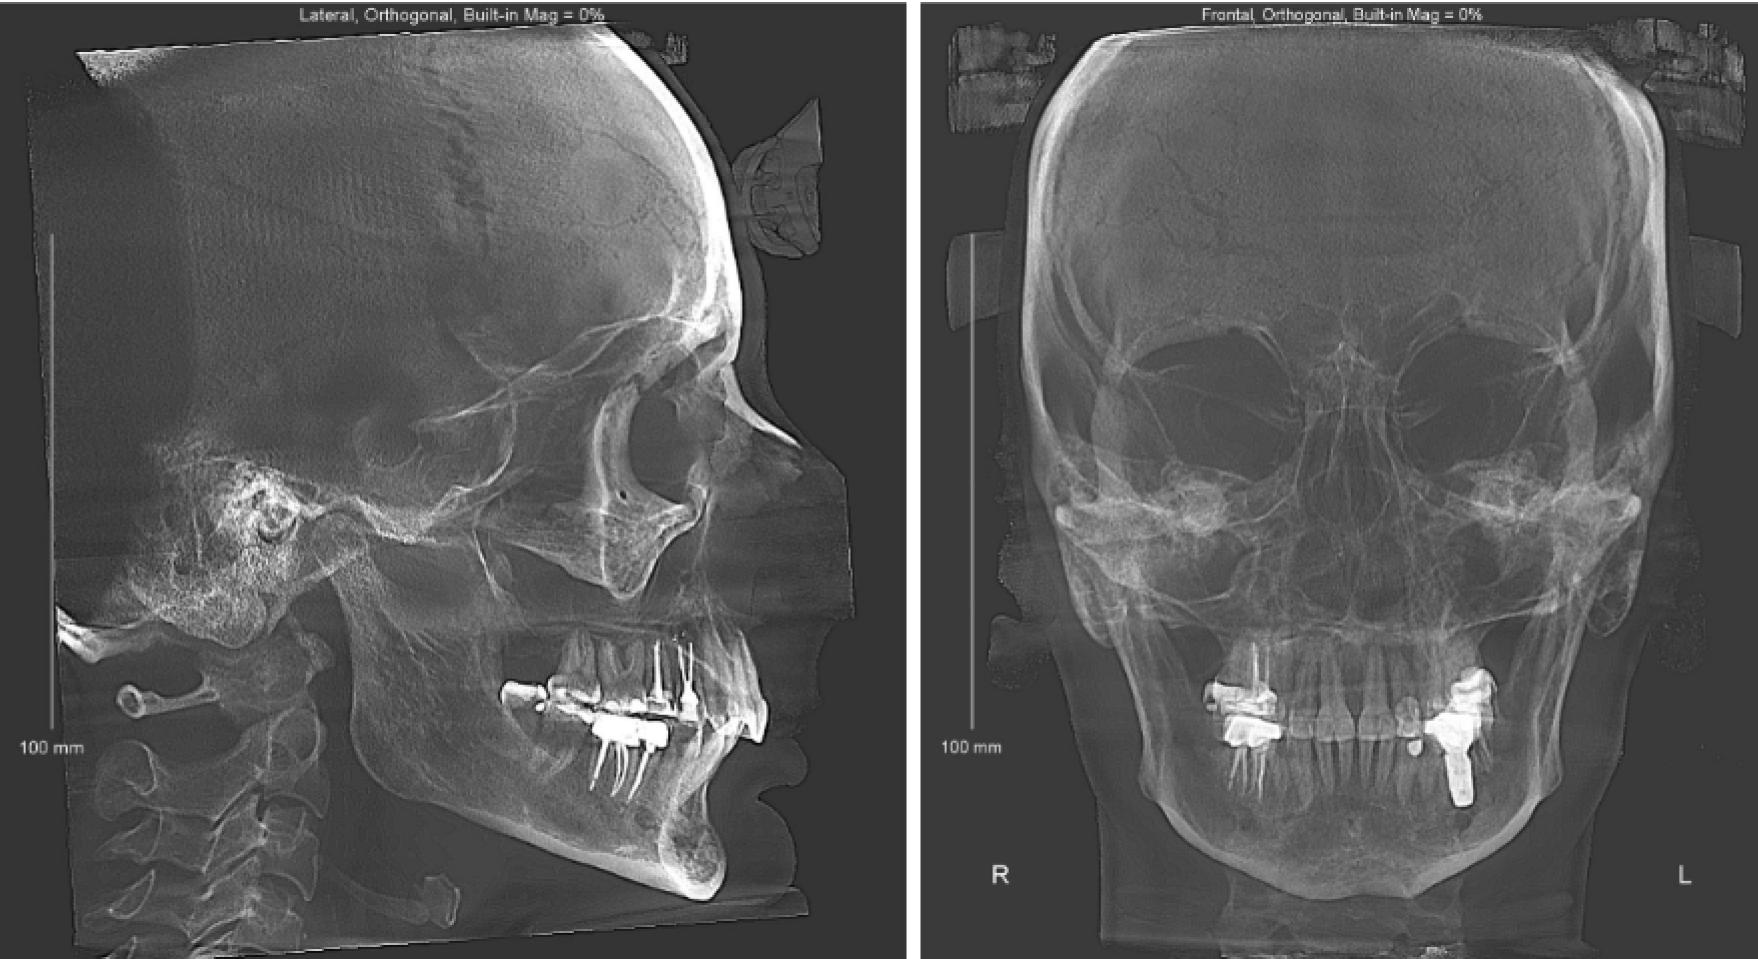

Телерентгенография — это метод рентгенологического исследования, используемый для детального изучения анатомии черепа и лицевого скелета в боковой и прямой проекции. Играет важную роль в стоматологии, давая специалистам возможность анализировать строение черепа, зубных единиц, а также соотношение челюстей и зубных рядов.

Телерентгенограмма дает специалисту возможность видеть не только зубы, но и челюсти, нежесткие ткани, а также углы между ними, такие как угол Бета. Это более детальное изображение, чем при обычном рентгене.

В телерентгенографии есть два основных типа исследований, которые на первый взгляд ничем не отличаются по виду, но показывают разные области челюстно-лицевой системы:

- ТРГ в боковой проекции. Это наиболее часто используемый вид исследования. Телерентгенограмма в боковой проекции показывает расположение обеих челюстей, а также положение зубных единиц относительно друг друга. Используется при диагностике нарушений смыкания зубов.

- ТРГ в прямой проекции. Помогает оценить симметрию лица. Используется для анализа асимметрии и деформаций костей черепа.

Она дает возможность увидеть различные анатомические структуры:

- Положение челюстей. Показывает, как они соотносятся друг с другом.

- Наклон и положение зубов. Позволяет оценить и выявить отклонения, которые нужно исправить в ходе ортодонтического лечения.

- Состояние костей. Показывает патологии костей лицевого черепа, такие как деформации или асимметрии.

- Угол Бета в ортодонтии. Этот угол используется для оценки положения зубных единиц и челюстного аппарата, что особенно важно при коррекции окклюзии.

Изображение предоставляет врачу-ортодонту полную картину состояния зубочелюстной системы, что делает его незаменимым при планировании ортодонтических процедур. Гармония черт лица и правильный прикус вычисляются математически. Это не что иное, как математическая основа диагноза, его геометрическое обоснование и одно из важнейших документальных подтверждений правильности поставленного диагноза.